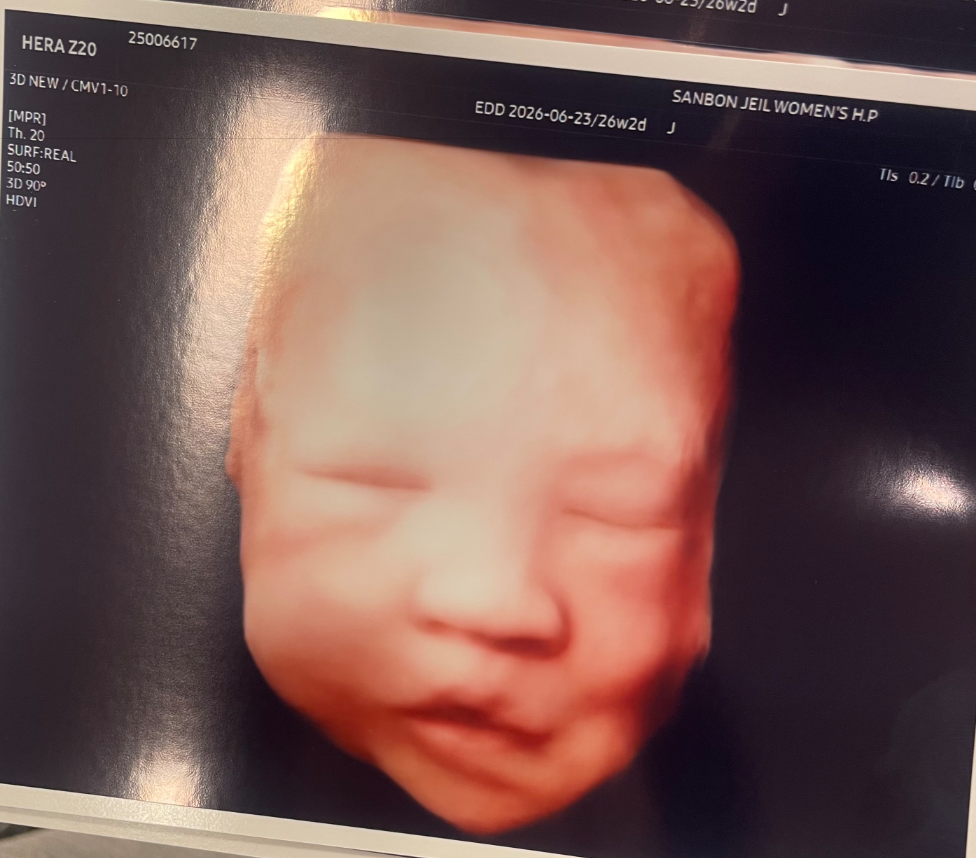

2. 2D 입체초음파 후기

입체초음파는 필수 검사는 아니고 선택 진료입니다. 즉 비급여라는 말씀!

두 종류가 있는데요. 기계가 새로 들어와서 AI 보정을 통해 화질이 더 좋아졌다고 하는 1안 - 9만원, 기존 입체초음파 7만원입니다.

저는 챗GPT로 화질 올리면되지 않을까? 싶어서 7만원 짜리 하려고 했더니 남편이 걍 9만원짜리 하자해서 9만원 짜리로 선택했습니다.

포도당을 들이키고 갔더니 저도 그렇고 아가도 그렇고 혈당 스파이크가 왔어요.

초음파 촬영 내내 하품을 쩍쩍 하더라는..

그 결과 뽑아주신 여러 사진 중에 하품사진만 두장 받았습니다.

하품하는게 넘 귀여웠고, 그나마 멀쩡한 사진을 보니 엄청 감흥있고 그러진 않더라고요.

남편을 닮은건지 저를 닮은건지도 긴가민가ㅋㅋ

집에와서 챗GPT로 입체초음파 사진 올리고 돌려보니 아주 예쁘게 포장해준 아기 사진을 만들어줬어요 ㅋㅋ

제발 이대로만 나와다오ㅋㅋ

입체초음파 사진은 다음 예약일에 1층 원무과에 방문하면 인생네컷처럼 인쇄해서 준다고 합니다.